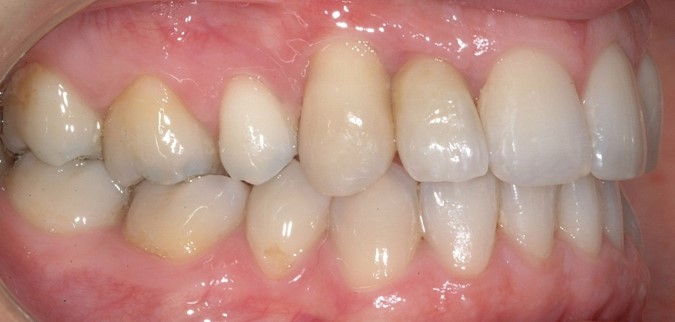

Al termine del trattamento ortodontico, che ha richiesto 24 mesi di terapia, è stata applicata una contenzione fissa3 all’arcata inferiore mediante filo multi-intrecciato coassiale .0195” esteso da 4.4 a 3.5 al fine non solo di stabilizzare il risultato sia sul piano orizzontale sia verticale, ma soprattutto per prevenire adeguatamente l’affollamento dentale terziario (Figure 9a-e).

Dopo tre anni dal termine del trattamento ortodontico, la paziente ha richiesto di finalizzare il suo caso; è dunque stata effettuata la sostituzione implanto-protesica dell’elemento 1.2, senza necessità di ulteriori rifiniture ortodontiche, avendo mantenuto, grazie al pontic in composito, un ottimo parallelismo radicolare tra 1.1 e 1.3.

È stata eseguita contestuale terapia rigenerativa, per ottimizzare qualità e quantità dei tessuti nel sito implantare. Come si rileva dalle immagini di follow up, dopo la fase implanto-protesica superiore, è stata applicata anche una parziale contenzione fissa tra gli incisivi centrali superiori e il risultato ortodontico si è mantenuto stabile nel tempo (Figure 10 a-e).